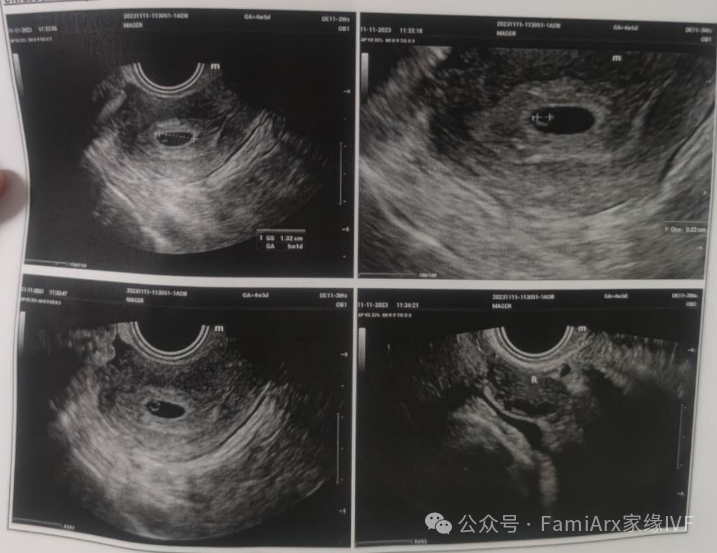

我还有着她第一次做B超检查子宫的视频

然后我们在10月23号,以10mm的很好的内膜指标进行了移植。